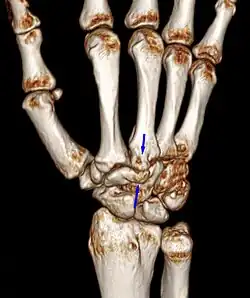

Carpal boss VR-3D-Reconstruction

Carpometacarpal bossing (or metacarpal/carpal bossing) is a small, immovable mass of bone on the back of the wrist. The mass occurs in one of the joints between the carpus and metacarpus of the hand, called the carpometacarpal joints, where a small immovable protuberance[1] occurs when this joint becomes swollen or bossed.

The carpometacarpal joint is usually found at the base of the second and third metacarpal bones at the point where they meet the small bones of the wrist.[2]